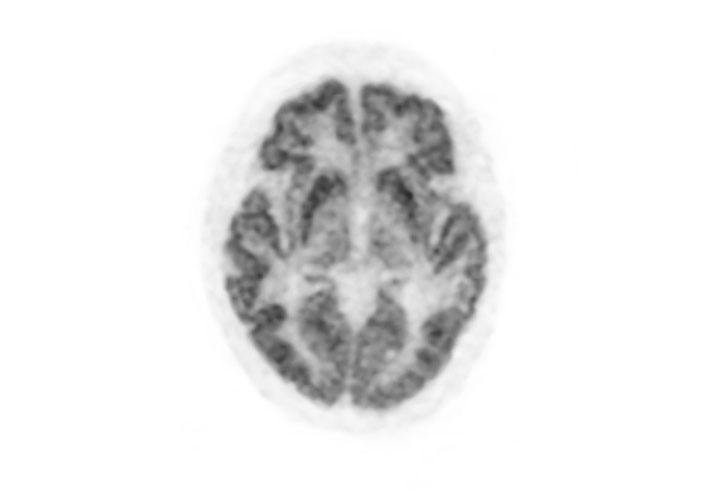

Coronal